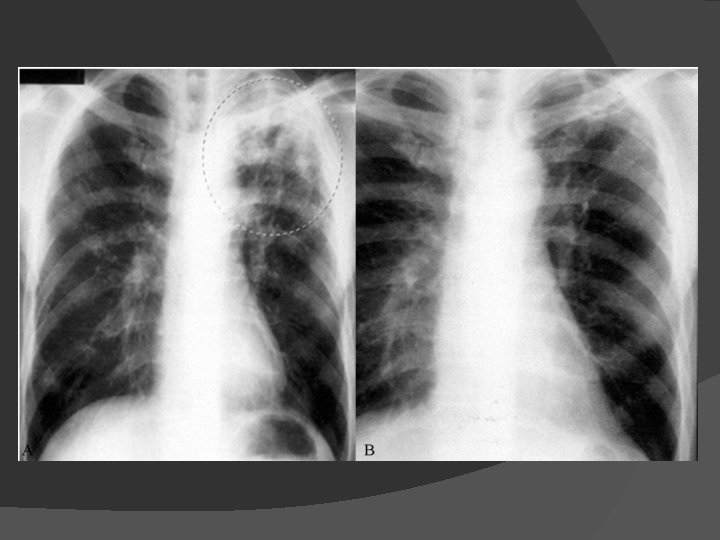

Signs, Symptoms and Diagnosis of TB X-ray • Sputum smear • microscopy Culture •

Diagnosis of pulmonary TB Sputum smear Acid fast stain (>10, 000 CFU/ml) Bronchoscopy Chest X-Ray Tuberculin skin testing (TST) National Cancer Institute. 2006 http: //www. nlm. nih. gov/medlineplus/ency/images/ency/fullsize/1607. jpg TMC 207: slide 29